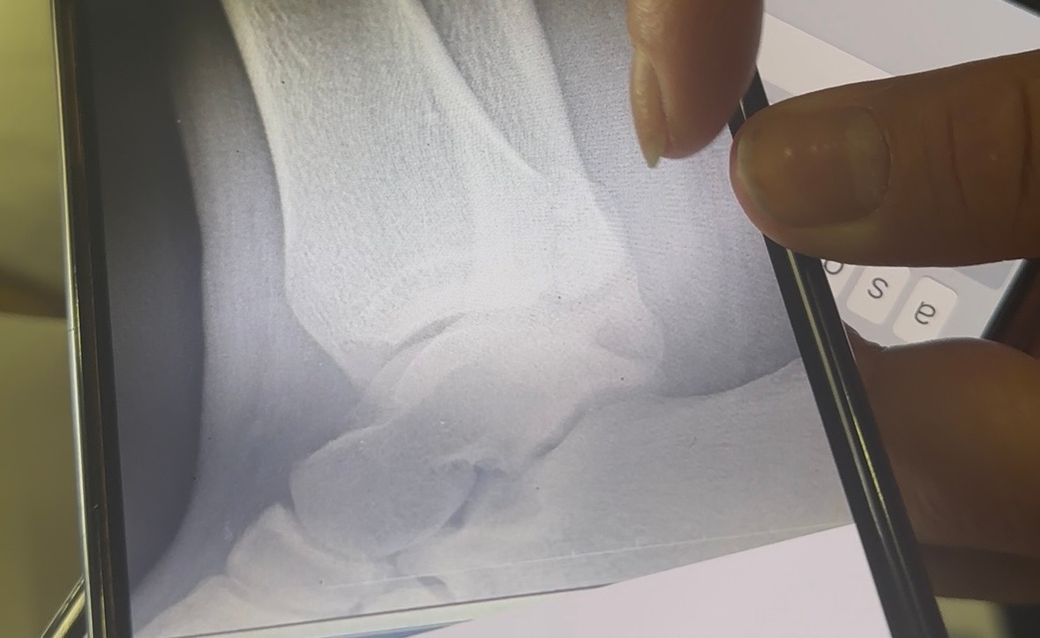

발목 골절 엑스레이사진 올립니다. 수술이 필요해보이는지요

발목이 골절되었습니다.

의사쌤들마다 의견이 나뉠수있지만 보셨을때 수술이 필요해보이는지 판단 부탁드립니다.

• 2번 째 사진

뼈 끝이 살짝 벌어지거나 어긋난 모습이 있어 "수술 가능성은 열려 있음"으로 보입니다.

그러나 전위가 아주 적고 관절면 정렬이 유지되면 "깁스로도 치료하는 경우가 있습니다."

CT(관절면) 확인이 중요하며 이를 기준으로 수술 여부가 결정됩니다.

"정렬 불량.관절면 깨짐.인대 불안정"이 있으면 수술, 아니면 보존적 치료가 가능합니다.